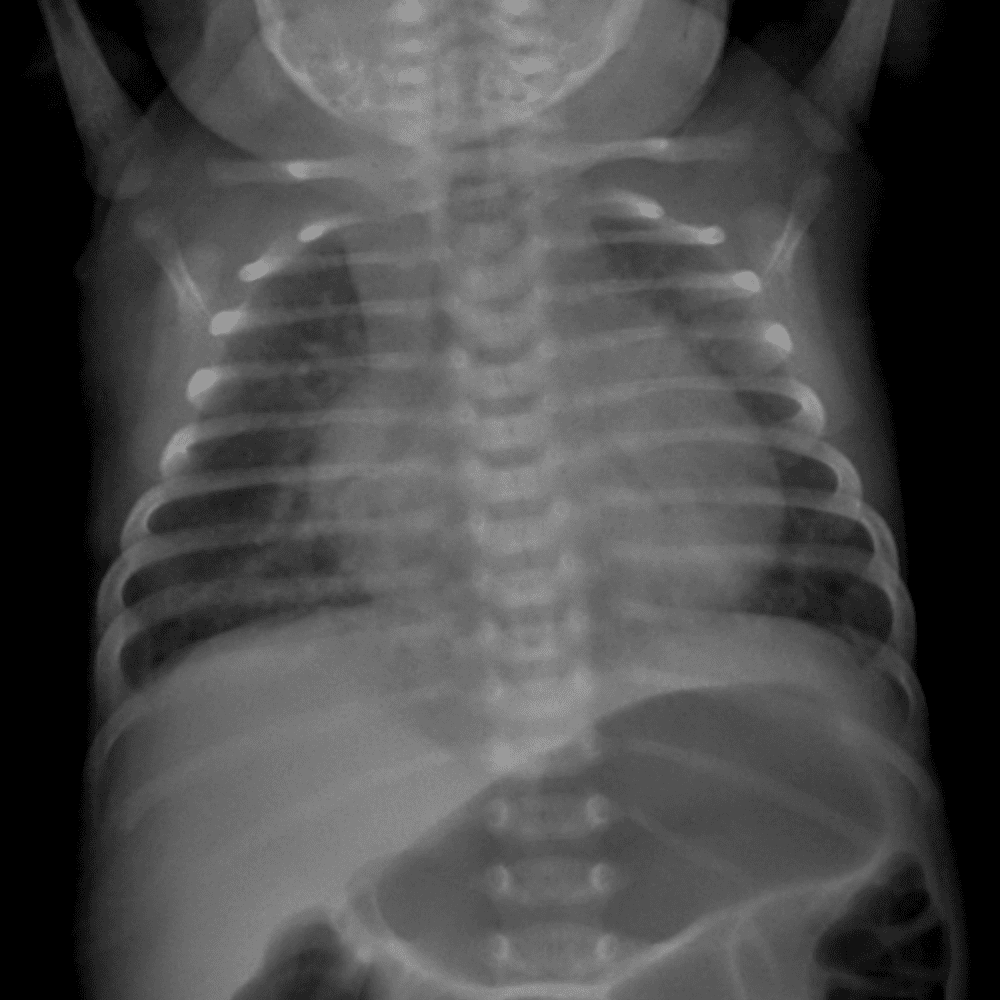

Peds Chest

Practice

Simulates call by including subtle or difficult cases and some normals.

50 cases